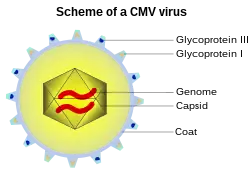

Human betaherpesvirus 5, also called human cytomegalovirus (HCMV),[2] is species of virus in the genus Cytomegalovirus, which in turn is a member of the viral family known as Herpesviridae or herpesviruses. It is also commonly called CMV.[3] Within Herpesviridae, HCMV belongs to the Betaherpesvirinae subfamily, which also includes cytomegaloviruses from other mammals.[4] CMV is a double-stranded DNA virus.[5]

HCMV replicates within infected endothelial cells[20] at a slow rate, taking about five days in cell culture.[21] It also infects fibroblasts, which requires expression of only a trimeric viral receptor complex, rather than the full pentameric complex that is required for infection of endothelial and epithelial cells.[22] Like other herpesviruses, HCMV expresses genes in a temporally controlled manner.[23][24] Immediate early genes (0–4 hours after infection) are involved in the regulation of transcription, followed by early genes (4–48 hours after infection) which are involved in viral DNA replication and further transcriptional regulation.[23] Late genes are expressed during the remainder of infection up to viral egress and typically code for structural proteins. While HCMV encodes for its own functional DNA polymerase, the virus makes use of the host RNA polymerase for the transcription of all of its genes.[25]

Synthesis of the viral double-stranded DNA genome occurs at the host cell nucleus within specialized viral replication compartments.[26]